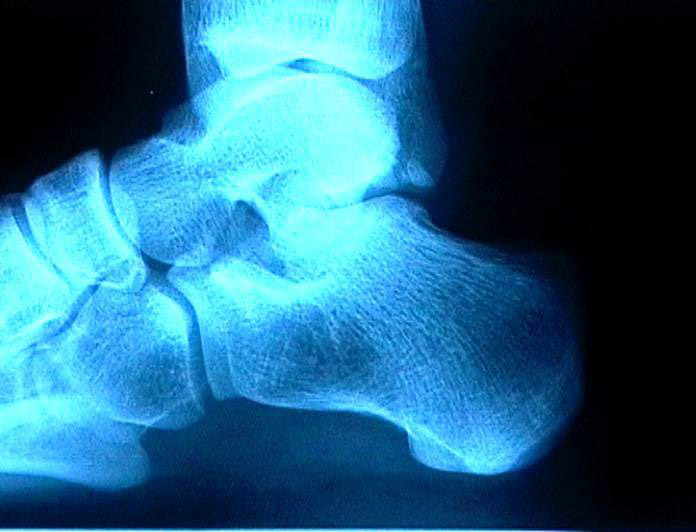

Bu bölgede ağrılar topuktan başparmağa uzanan plantar fasia olarak adlandırılan adalede oluşur. Plantar fasitis (subkalkaneal ağrı): Çok fazla koşma ve zıplama, ayak parmaklarından topuk kemiğine uzanan adale bantlarının (fascia) inflamasyonuna neden olur. Ağrı topuğunuzun altında ve merkezinde toplanır, başlangıçta orta derecededir, fakat gece boyunca dinlenmenizden sonra ilk adımı attığınızda, aniden şiddetlenir. Topuk Dikeni)

Plantar fasiitis uzun süre devam ederse fascia doku bantlarının topuğa bağlandığı yerde, bir topuk dikeni (kalsiyum tortusu) şekillenir. Bu kolaylıkla çekilen bir röntgende görülebilir. Tedavi çoğunlukla, plantar fasiitisle aynıdır.

Sol taraftaki resme bakarak sizlere anlatmak istiyorum.Kırmızı kalemle yuvarlak içine alınan kalsiyum tortusunu dorn terapi yöntemiyle dağıtıyoruz.Dağıttıktan sonra o bölgede acıya neden olan siniri (el terapi) yöntemiyle mavi yuvarlağın içersine birkaç maniplasyon hareketiyle yerine getiriyoruz..Pelvis kemiklerini dengeye getirdikten sonra bir kaç dakikalık masaj tekniği ile sorunlu bölge ortadan kalkıyor.Ayağa kalktığınız da daha ilk seansta yüzünüz gülmeye başlıyor ve ayağınızın topuğunu korkusuzca yere basıyorsunuz.Terapi olmak için hala bekliyormusunuz?